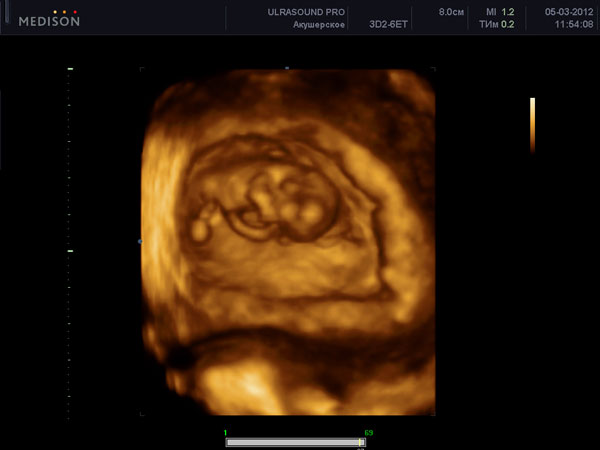

Допологова (антенатальна) передача герпетичної інфекції плоду виникає в 5% випадків від матерів з первинною формою генітального герпесу. При первинній формі генітального герпесу існує період, коли вірус герпесу з'являється у великих кількостях в крові вагітної і таким чином передається через плаценту плоду.Етот механізм внутрішньоутробного інфікування характерний і для інших TORCH-інфекцій (TORCH (toxoplasmosis, other infections, rubella, cytomegalovirus, and herpes simplex). При цьому у плода можуть виникати такі вади розвитку як мікроцефалія, мікроофтальмія, внутрішньочерепні кальцифікати і хореоретініт.